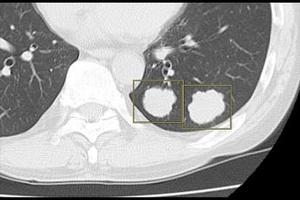

(4)AI技術を活用して開発した読影支援機能を「医療クラウドサービス」で利用可能

「医療クラウドサービス」は,「SYNAPSE LEAD Cloud」からクラウドサーバーにアップロードされた画像に対し,選択した読影支援機能の解析結果をビューワ上で参照できるサービス。ユーザー登録後,専用ポータルサイトから「胸部X線CADサービス」や「肺結節検出サービス」など,5つの解析機能の中から必要なものを選択するだけで,簡単に利用できる。料金プランは,利用回数に応じた従量課金と,一定期間利用できる定額利用の2種類を用意しており,導入コストを抑えながら,目的や運用に応じた柔軟な活用が可能である。さらに,本格導入前に無料トライアルから利用を開始することもできる。

胸部X線CADサービス*6 |

肺結節検出サービス*7 |

肋骨骨折検出サービス*8 |

頭部高吸収/低吸収強調フィルタサービス*9 |

腹部吸収値強調フィルタサービス*10 |

*6 胸部X線CADサービス(CXR-AID)は,「胸部X線画像病変検出ソフトウェア CXR-AID」の【類型1】によって提供されるサービス。販売名:胸部X線画像病変検出(CAD)プログラム LU-AI689型 承認番号:30300BZX00188000

*7 肺結節検出サービスは,肺結節検出プログラム FS-AI688型で実現している。本サービスに含まれる肺結節性状分析機能は画像診断ワークステーション用プログラム FS-V686型,肺区域ラベル機能は画像処理プログラム FS-AI683型で実現している。

*8 肋骨骨折検出サービスは,肋骨骨折検出プログラム FS-AI691型で実現している。本サービスに含まれる肋骨ラベル機能は画像処理プログラム FS-AI683型で実現している。

*9 頭部高吸収/低吸収強調フィルタサービスは,画像処理プログラム FS-AI683型で実現している。

*10 腹部吸収値強調フィルタサービスは,画像診断ワークステーション用プログラム FS-V686型と画像処理プログラムFS-AI683型で実現している。